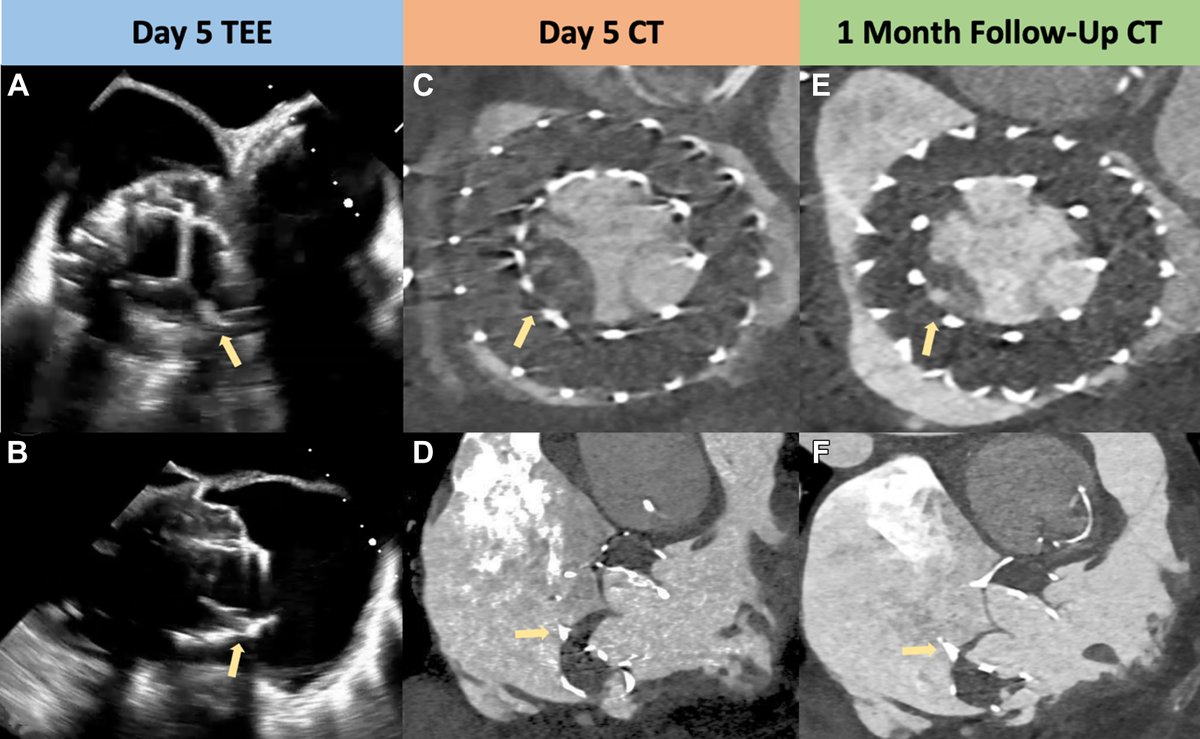

FANTASTIC MUST-READ #JACCIMG @JACCJournals SOTA review on Post #Evoque #TTVR Echo #TTE imaging. Comprehensive, practical! Download full paper here FREE for a LIMITED TIME! https://t.co/lfhJ0khJAw https://t.co/DgyCXnMOOF